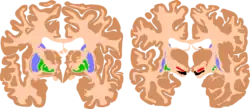

| The basal ganglia plays essential roles in voluntary motor function. Various forms of damage to the basal ganglia can cause a range of movement disorders. | |

Like other forms of CP, it is primarily associated with damage to the basal ganglia in the form of lesions that occur during brain development due to bilirubin encephalopathy and hypoxic–ischemic brain injury.[7]

CP in general is a non-progressive, neurological condition that results from brain injury and malformation occurring before cerebral development is complete.[3] ADCP is associated with injury and malformations to the extrapyramidal tracts in the basal ganglia or the cerebellum.[7] Lesions to this region principally arise via hypoxic ischemic brain injury or bilirubin encephalopathy.[7]

Hypoxic-ischemic brain injury is a form of cerebral hypoxia in which oxygen cannot perfuse to cells in the brain. Lesions in the putamen and thalamus caused by this type of brain injury are primary causes of ADCP and can occur during the prenatal period and shortly after.[7] Lesions that arise after this period typically occur as a result of injury or infections of the brain.[18]

Bilirubin encephalopathy, also known as kernicterus, is the accumulation of bilirubin in the grey matter of the central nervous system. The main accumulation targets of hyperbilirubinemia are the basal ganglia, ocular movement nucleus, and acoustic nucleus of the brainstem.[7] Pathogenesis of bilirubin encephalopathy involves several factors, including the transport of bilirubin across the blood–brain barrier and into neurons.[7] Mild disruption results in left cognition impairment, while severe disruption results in ADCP.[7] Lesions caused by accumulation of bilirubin occur mainly in the global pallidus and hypothalamus.[7] Disruption of the blood–brain barrier by disease or a hypoxic ischemic injury can also contribute to an accumulation of bilirubin in the brain.[7] Bilirubin encephalopathy leading to cerebral palsy has been greatly reduced by effective monitoring and treatment for hyperbilirubinemia in preterm infants.[7] As kernicterus has decreased due to improvements in care, over the last 50 years the proportion of children developing athetoid CP has decreased.[19] In most cases, will have normal intelligence.

Multiple classification systems using magnetic resonance imaging (MRI) have been developed, linking brain lesions to time of birth, cerebral palsy subtype and functional ability.[23][24][25][26] Around 70% of patients with DCP show lesions in the cortical and deep grey matter of the brain, more specifically in the basal ganglia and thalamus. However, other brain lesions and even normal-appearing MRI findings can occur, for example white matter lesions and brain maldevelopments.[2][25][27][28] Patients with pure basal ganglia and thalamus lesions are more likely to show more severe choreoathetosis whereas dystonia may be associated with other brain lesions, such as the cerebellum.[2] These lesions occur mostly during the peri- and postnatal period since these regions have a high vulnerability during the late third trimester of the pregnancy.[29] Unfortunately, contemporary imaging is not sophisticated enough to detect all subtle brain deformities and network disorders in dystonia. Research with more refined imaging techniques including diffusion tensor imaging and functional MRI is required.[10][30]